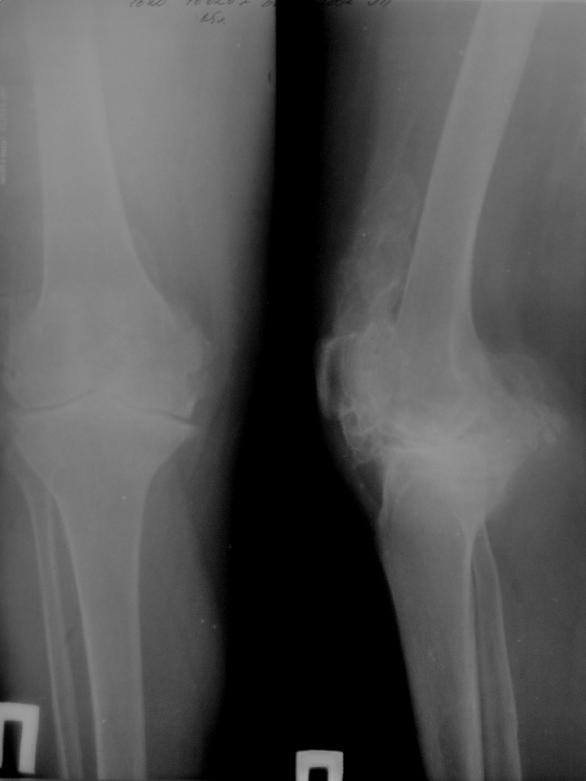

Уважаемые коллеги!Возможно ли протезирование в данной ситуации, пациентке 65 лет.

Технически протезирование в данной ситуации на мой взгляд вполне возможо. Только по Р-гр. оценить состояние сгибательно-разгибательного аппарата, стойкость и длительность контрактуры коленногосустава невозможно. Поэтому сложно прогнозировать процесс реабилитации пациента.